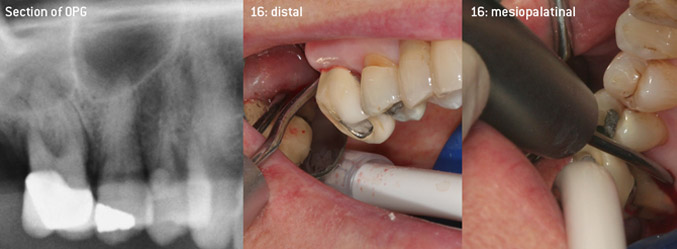

As initiators of the development of the new diamond-coated 3AP air scaler tip, the two dentists recognized the need for improvement of the handling restrictions of the commercially available diamond-coated tips, especially during furcation treatment and when working in tight intraosseous pockets. This should be possible for both non-surgical (Figure 2) and surgical (Figure 3) procedures.

(Fotos (Figures 2 -4): © Dr. Christian Graetz)

The aim was to develop a universally applicable tip in order to avoid time-consuming tip changes. In addition, it should be easier to use the new working tips in tight intraosseous pockets from distal and at the distal furcation entrance of maxillary molars, allowing more effective use of instruments as a result. This was achieved by employing an instrument curve with a larger diameter (Figure 1), which is highly advantageous for closed debridement on teeth with advanced attachment loss and involvement of furcation in particular (Figure 4).